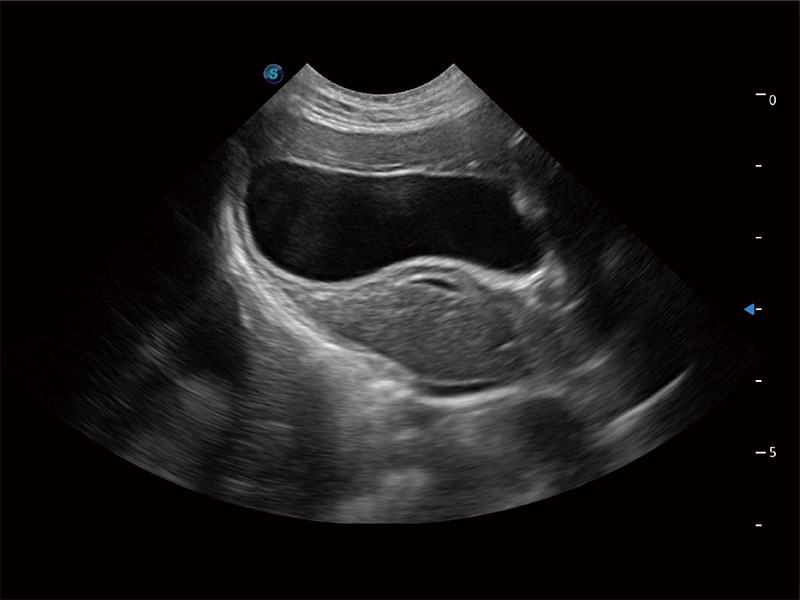

动物是人类最亲密的朋友和最值得信赖的伙伴。乐玩lewin国际也一直致力于探索动物专用的超声影像解决方案。全新推出的ProPet系列,是乐玩lewin国际在动物超声影像智能化、专业化、精准化的一次跨越式革新。动物不能用言语来表述自己的不适,通过超声影像,ProPet系列搭建了动物医生与不同物种沟通的“桥梁”,为动物医生注入了“治愈之力”。 ProPet 80 是乐玩lewin国际匠心打造的一款高端动物专用彩超,采用性能卓越的全新硬件架构,极大提升超声系统的运行效率和数据处理能力,帮助动物医生从容应对日益增多的挑战性病例和日益多样化的临床需求。

高性能和先进的临床应用工具可以为动物医生提供临床信心。ProPet 80 搭载了先进的腹部和浅表应用工具,帮助医生在日常临床实践中发挥前所未有的作用。

ProPet 80 全新的动物超声智能软件和丰富的探头群,为动物医生提供了高清晰度和精细分辨率的图像,无论在宠物、马科、畜牧还是实验室动物等应用中都可以轻松应对,为您的日常工作带来满意的体验。